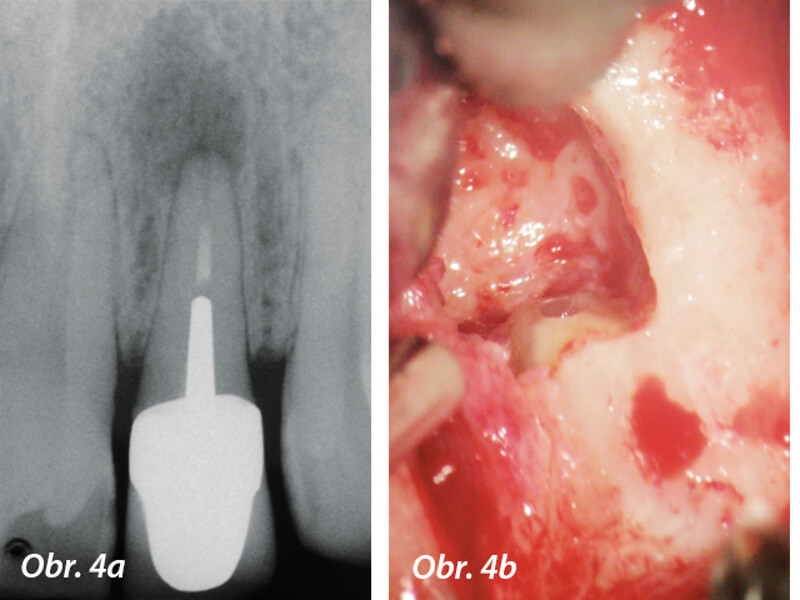

Aplikace MTA s použitím Produit Dentaires (PD) MAP System